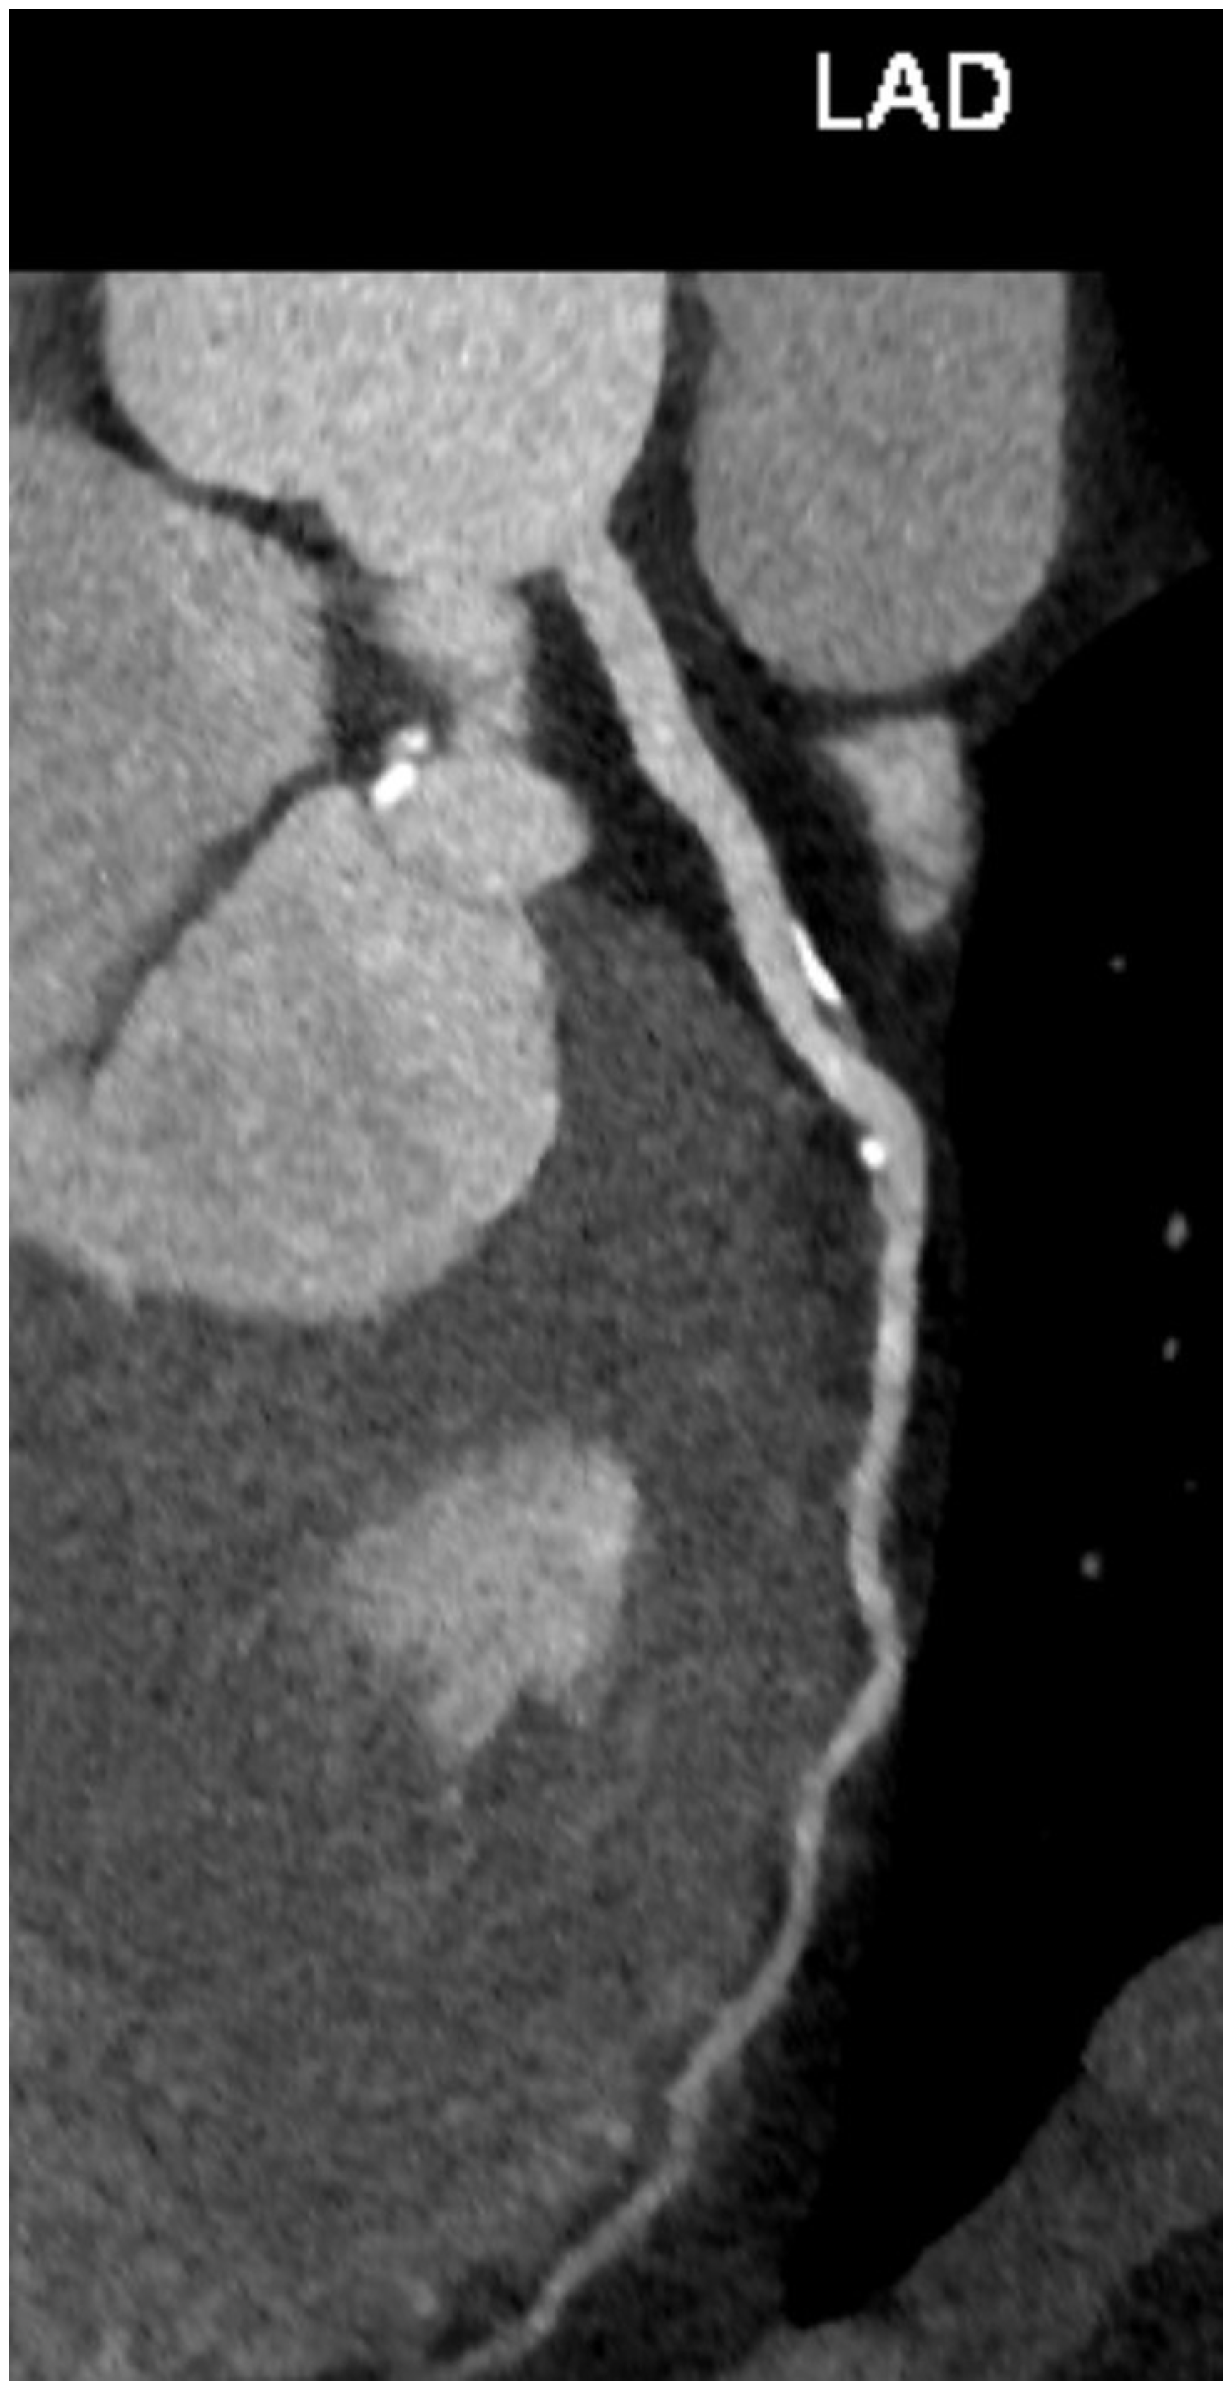

Other CT manifestations of aging coronary arteries include a higher rate of intraplaque hemorrhage, rupture, and the presence of high-risk plaque features [72]. Currently, contrast-enhanced CT coronary angiography is not recommended in asymptomatic persons for the assessment of occult coronary artery disease. According to the results of the prospective multicenter international CONFIRM long-term study, there is no further incremental value offered by coronary CT angiography when its findings were added to a model incorporating CVD risk factors and CAC score [73]. However, some authors suggest that coronary CT angiography could be the best and definitive method to guide patients and physicians in the prevention of coronary artery disease because it provides additional information beyond coronary artery calcification, including the burden of all plaque types, high-risk plaque features, and in the future, the addition of machine learning and radiomic plaque characteristics (Figure 5) [74]. Additional CT applications are emerging with novel dual-energy CT (DECT) technology, including CAC scoring from virtual non-contrast imaging, better differentiation between calcified- and non-calcified plaques, more precise evaluation of high-risk plaque features, and calcium-extraction algorithms that enable more accurate stenosis quantification in the presence of calcified plaques [75]. Furthermore, using DECT, it is possible to create iodine myocardial maps that may depict myocardial perfusion defects and late-enhancing scar tissue, improving diagnostic accuracy for myocardial ischemia and infarction [75,76].

Figure 5.

An incidental finding of left anterior descending (LAD) coronary artery plaques on a CT angiography performed in a 44-year-old male patient with a bicuspid aortic valve, dilated ascending aorta, and moderate aortic regurgitation.